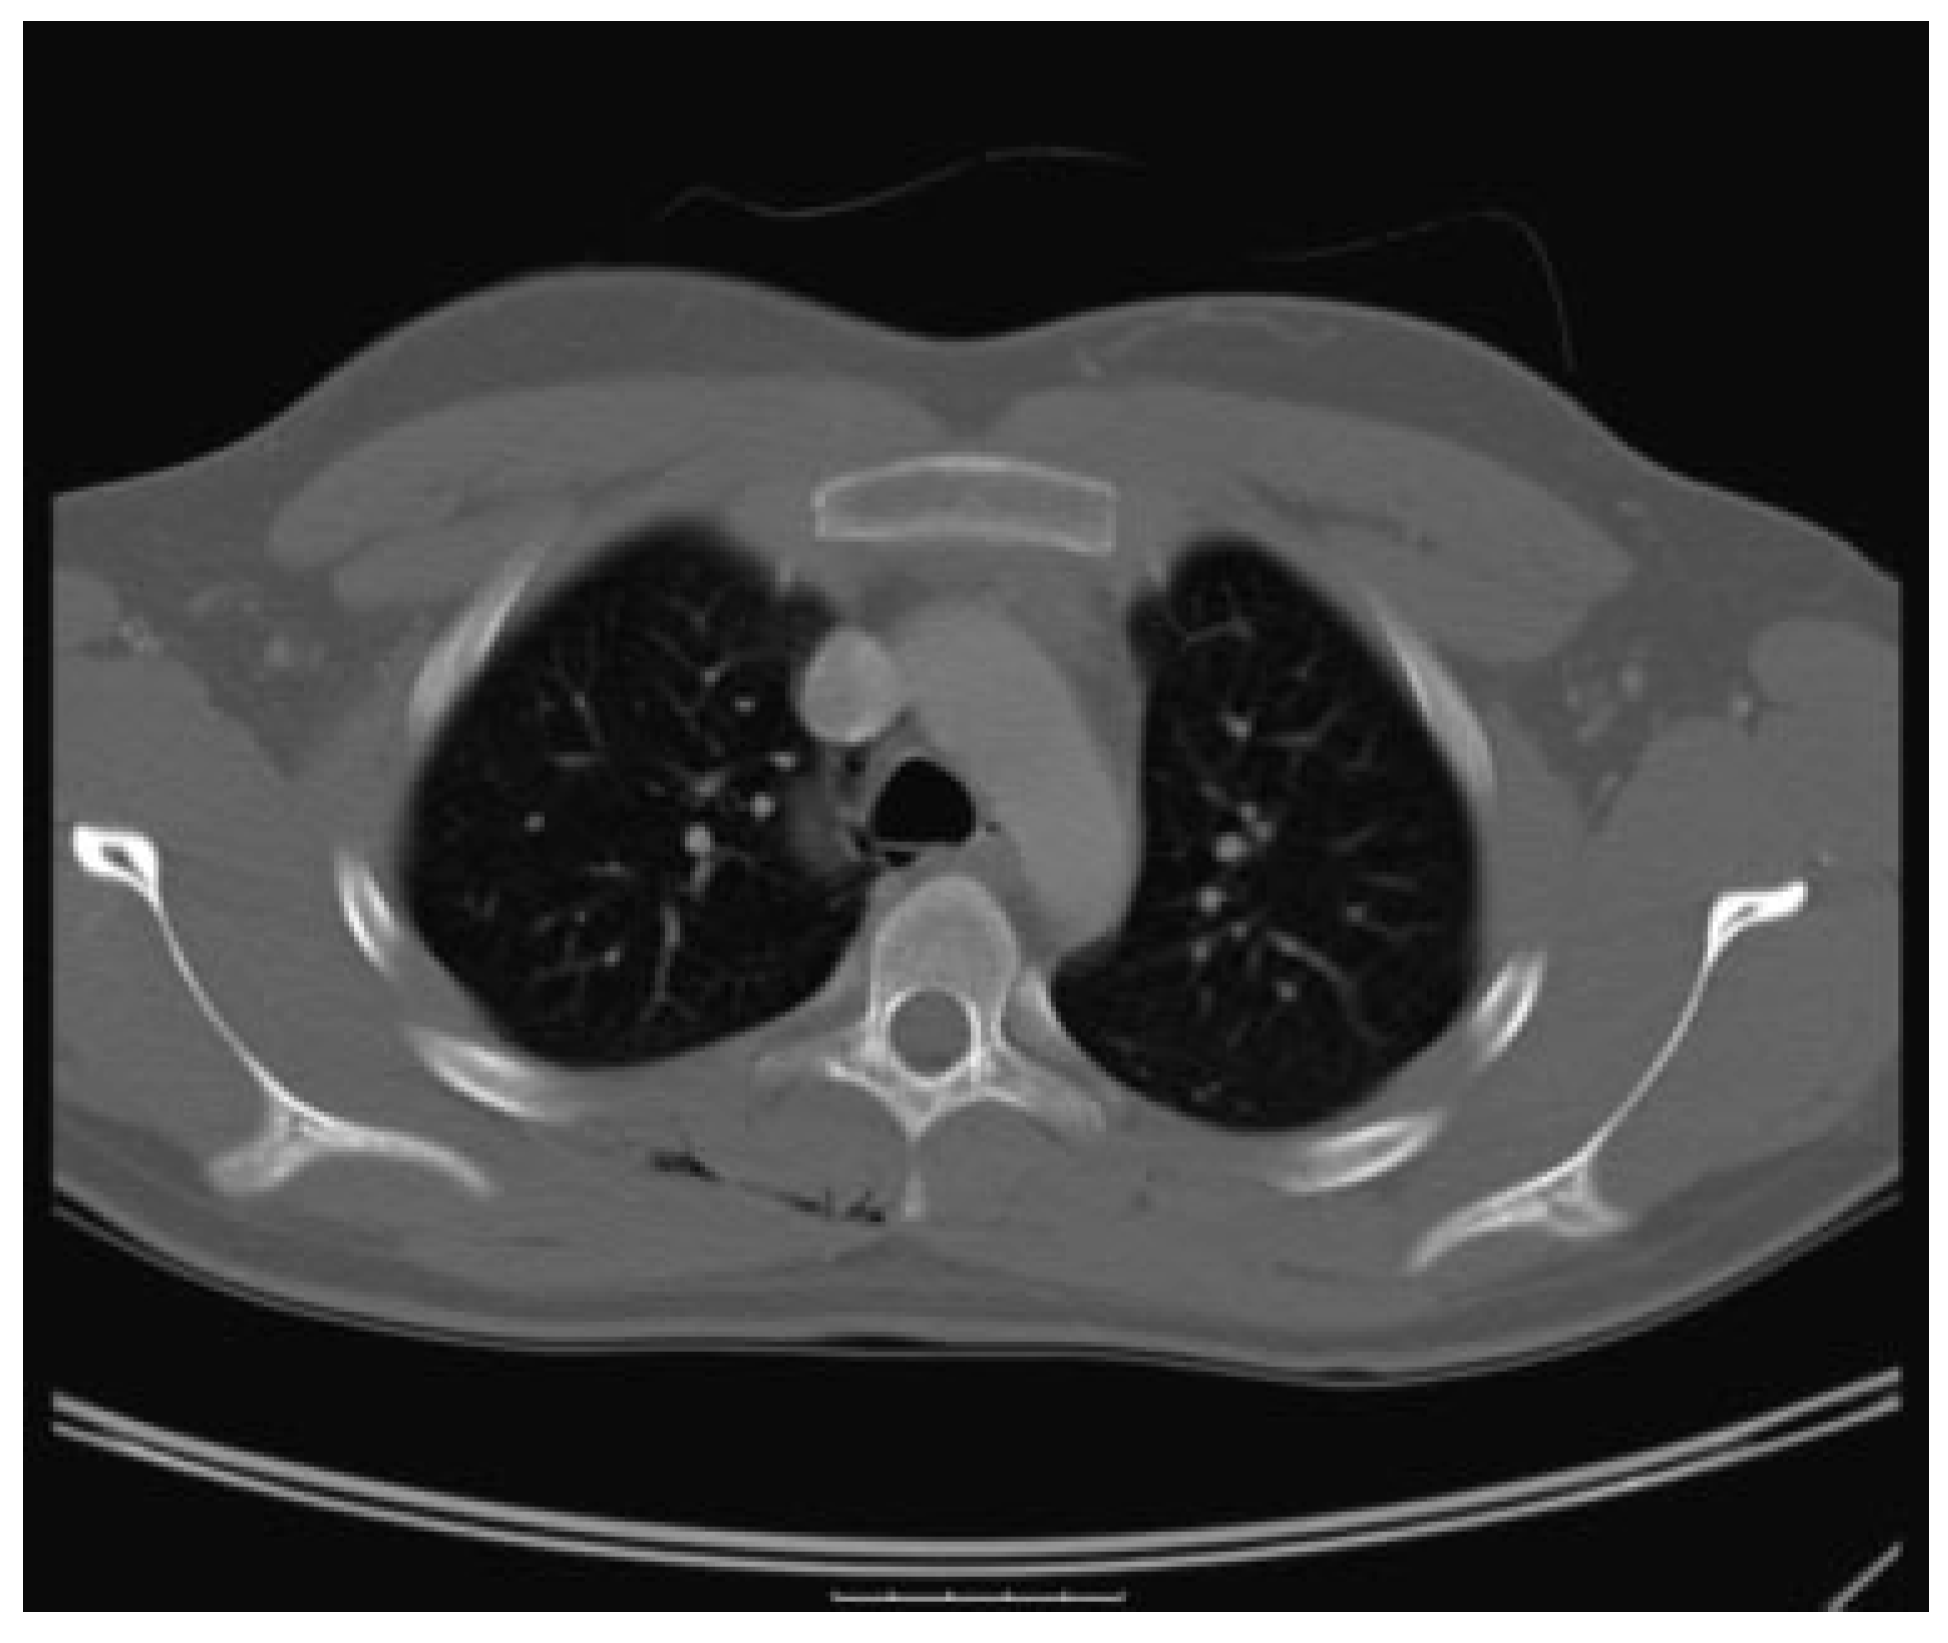

Chest CT scan demonstrated inferior extension of the softtissue air into the superior mediastinum and right posterior upper chest wall (Figure 4).

Figure 4. Air within mediastinum around the trachea and aorta. Traces of gas can be seen in the posterior chest wall.